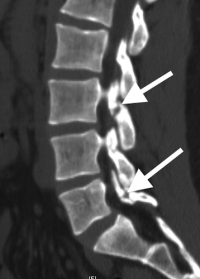

(Click to Enlarge Image) CT scan of healed pars fracture. White arrow points to healed fractureWhite dot in bone is tip of screw used for repair.